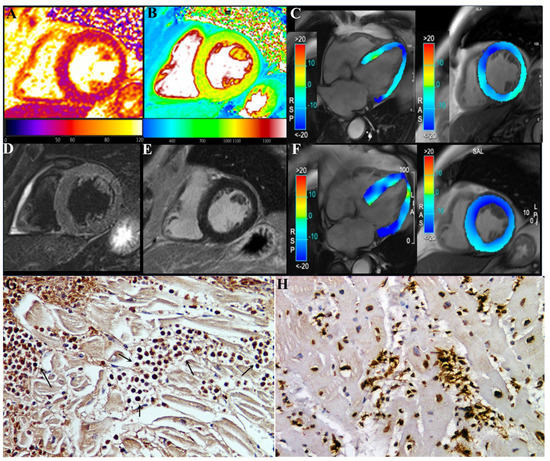

CMR showed in our three patients a diffuse increase in both T2 and T1 myocardial value, as a result of diffuse inflammatory involvement (Figure 2 and Figure 3). LGE was present as well and patchily distributed in the subepicardial myocardium. Severe compromise of LV contractility of 35 and 28% was registered in pt2 (Figure 3) and pt3, respectively.

Patient serum showed an increase in serum cation protein levels in all patients (23.4 ± 17 U/mL) versus controls (6.1 ± 1 U/mL), p = 0.079.

The three patients received prednisone 1 mg/kg die for 3 days tapered to 0.33 mg/kg for 4 weeks. At the end, a new noninvasive cardiac evaluation, including ECG, Holter and cardiac magnetic resonance, was undertaken. Pt1 remained in junctional rhythm but without abnormal pauses and requiring pacemaker implantation. Pt2 and pt3 manifested a complete recovery of cardiac function, with LVEF rising to 49.5 % (from 35%) and 56% (from 28%), respectively.

Figure 3. A 78-year-old male (pt2) with eosinophilic myocarditis myocarditis after second dose of COVID-19 mRNA (BNT162b2) vaccine. At first CMR exam (AE), performed 4 weeks after symptoms onset, T2 (A) and native T1 (B) maps revealed an increase in global T2 (55 ms ± 4 ms, normal range < 49.9 ms) and T1 (1060 ± 15 ms, normal range < 1027 ms) myocardial values, without any noticeable focal areas of signal changes on STIR T2-weighted (D) and late-gadolinium-enhanced (E) images, reflecting mild diffuse edematous condition. CineMR images, acquired on four-chamber (left) and mid-ventricular short-axis (right) views, analyzed by tissue tracking analysis show moderate impairment of both longitudinal and circumferential systolic left ventricular function (GLS: −12.3%, GCS: −13.6%, EF: 35%) at admission (C), which improved at two-month follow-up after therapy ((F), GLS: −18.1%, GCS: −17.8%, EF: 49.5%). GCS: global circumferential strain; GLS: global longitudinal strain; EF: ejection fraction. (G) shows in post-vax myocarditis massive eosinophilic myocardial infiltration with necrosis of the adjacent myocytes (IHC for eosinophil major basic protein (EMBP) antibody). (200× magnification). (H): Comparison with acute myocarditis associated to COVID19 infection showing intense lymphocytic inflammation (IHC for CD45Ro) (200× magnification).